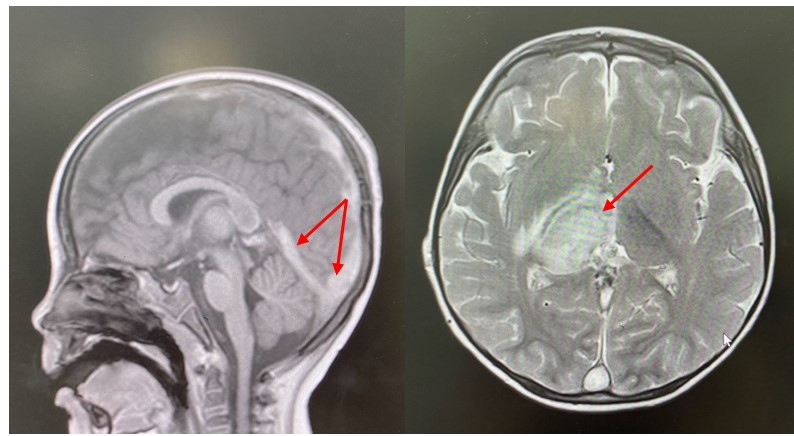

Hình ảnh huyết khối và tổn thương não trên phim MRI não của bệnh nhi - Ảnh: BV Nhi Đồng 1

Chụp CT, MRI sọ não phát hiện huyết khối tĩnh mạch nội sọ, còn gọi huyết khối xoang tĩnh mạch não. Đây là tình trạng hình thành cục máu đông trong hệ thống tĩnh mạch dẫn lưu máu từ não, khá hiếm gặp nhưng là một nguyên nhân gây đột quỵ ở trẻ em, với tỷ lệ tử vong lên đến 10% và khoảng 40% trẻ sống sót có di chứng thần kinh.